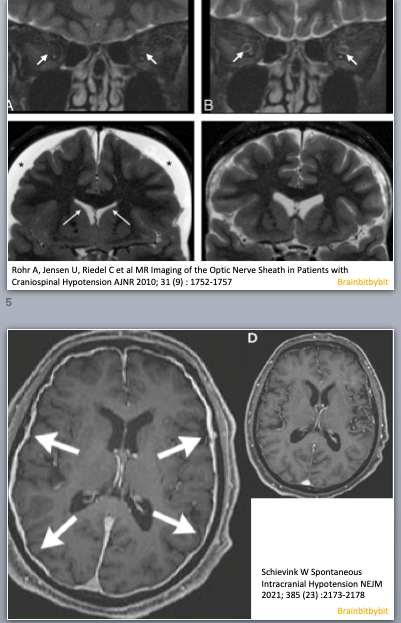

Figure 1 Coronal (above) and sagittal (below) T1 weighted images showing the lateral ventricles (lat), third (III) and fourth ventricle (IV) and several subarachnoid cisterns. The temporal horn of the lateral ventricle is anatomically close to the subarachnoid space, more specific the choroid fissure.

The brain and spinal cord are surrounded by 3 layers of connective tissue: (1) the pia, lying direct against the parenchyma (2) the arachnoid, which is an avascular layer bridging the cortical sulci and bridging the distance to the skull and (3) the dura mater consisting of an outer periosteal layer and an inner meningeal layer. The arachnoid and the space between the arachnoid and pia houses CSF. The widenings in the subarachnoid space called cisterns seemed like topography: something to memorize without the need for deeper knowledge.